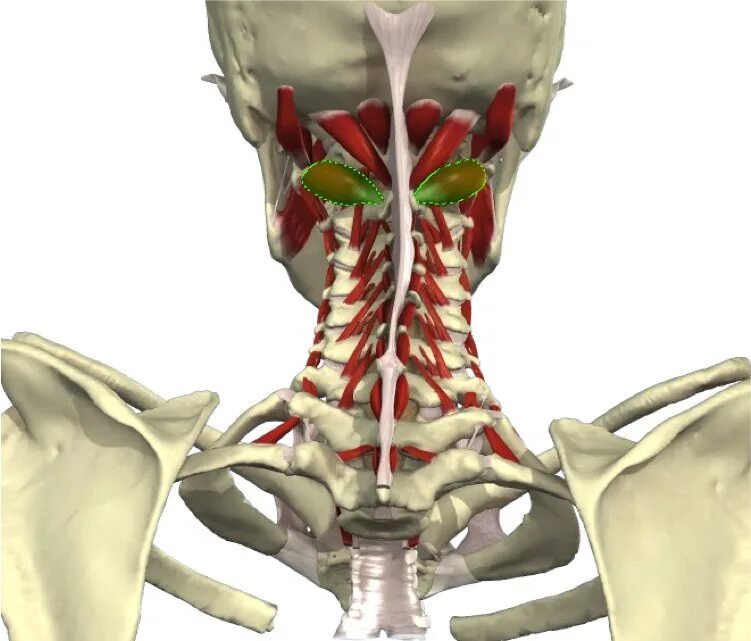

Асимметрия сегментов v2 позвоночных артерий